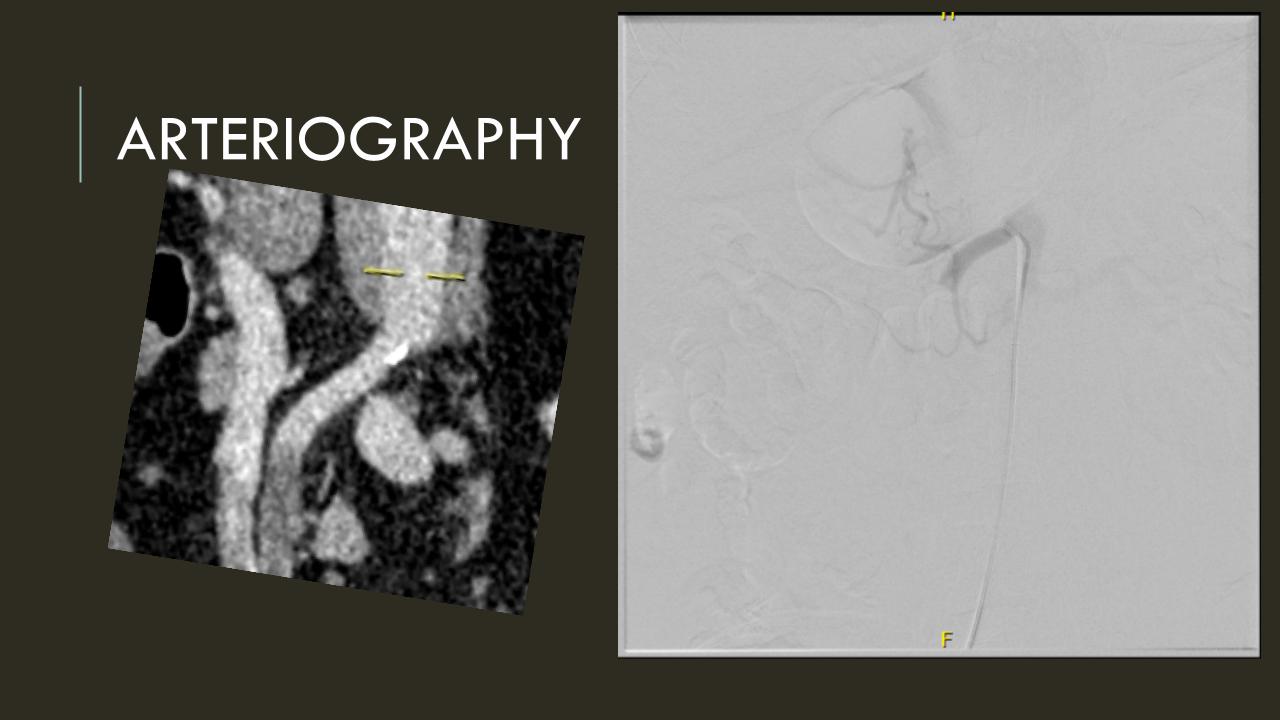

The EVAR was performed percutaneously. No endoleak was detected by completion arteriography (figure). He was soon discharged and was grateful. In followup, CT scan showed excellent coverage of the proximal and distal zones and absence of type III endoleaks. There was increased density to suggest a type II leak, but his inferior mesenteric artery was not the source of it. over a three year period, his aneurysm sac continued its 2-3mm of annual growth despite the presence of the the stent graft.